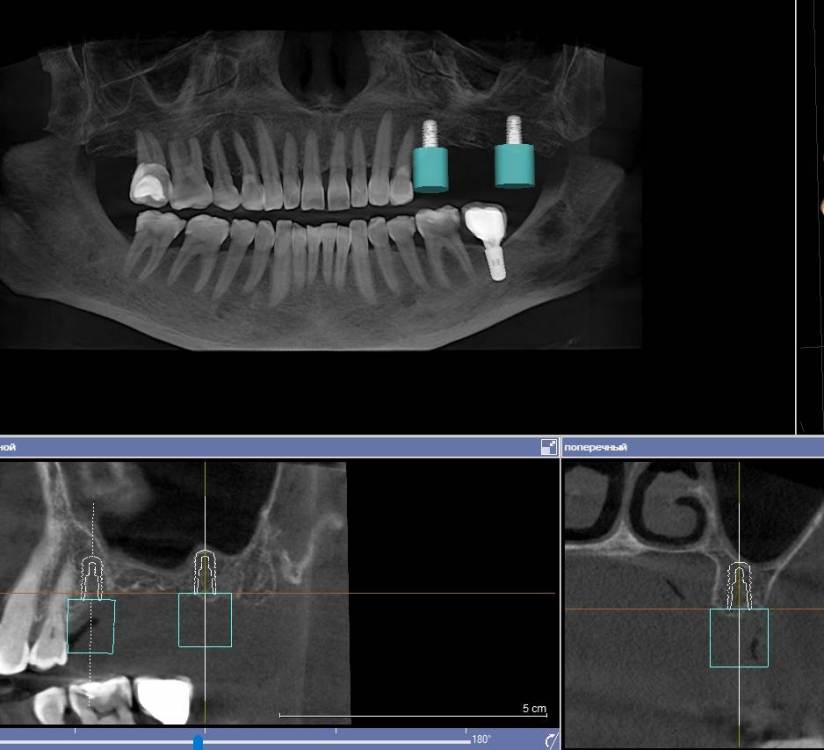

Ponchik Опубликовано 28 апреля, 2021 Поделиться Опубликовано 28 апреля, 2021 Добрый день. Показываю мой новый опыт ? для многих на форуме это рутина, но может кому-то интересно(полезно) будет. 1. Сделано КЛКТ, в GalileosViewer примерное планирование из расчёта избежать синуслифтинг (очень против пациентка). 3.7 на КТ моя работа два года назад. Выявлен новый кариес на дистальной у 3.6. 2. Сделал скан на primescan 3. Планирование далее в другой лаборатории. Наш техник пока не смог в 3д принтер (Надо самому освоить) Пришлось долго переписываться. Так как в дайкомоских файлах нет оказывается плана на имплантацию. Он не передаётся. 4. Изготовили и доставили шаблон. 5. Итоговая работа - 2.5 - штрауманн бл 4.1-8 2.7 - штрауманн бл 4.8-8 с небольшим поднятием остеотомом дна. Поднимал даже не стуча, продавилось остеотомом. Замечания: шаблон сел хорошо, особенно когда отломились резцы ))). Обговорить поперечные балки с техником я не догадался и на резцах шаблон и заканчивался. Дистальная часть заметно двигалась вверх, вниз. Вставить фрезу с надетым шаблоном, нереально в области 2.7, 2.8. рот так не открывается (эх, был бы это Мик Джагер) попробовал втавить фрезу в шаблон, а потом наконечник прищёлкнуть, не смог. Всё равно не влезть. поэтому дистальная втулка использовалась как направляющая для грифеля карандаша. Ну хоть так шаблон, но помог. Передняя втулка довольно легко выдвигалась. Не подклеивал ни как. Вывод: не смотря на неудобства, считаю шаблон мне очень помог. Учитывая огромную толщину слизистой и хз как я бы там на глаз наставил. А так даже без вертикальных разрезов работал. 3 2 Ссылка на комментарий